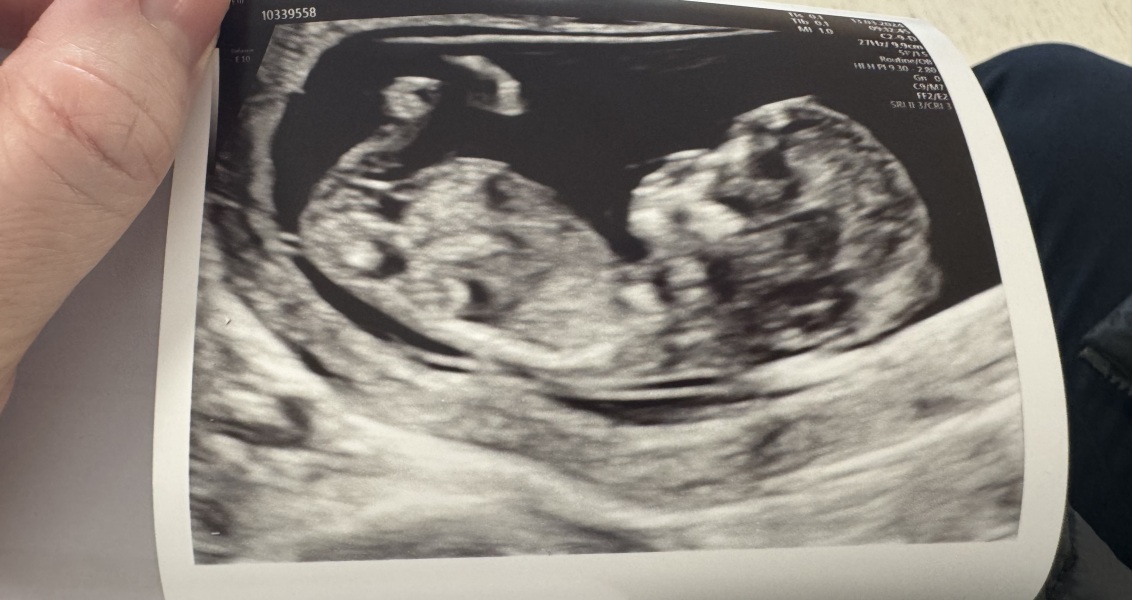

We had our scan this morning and all is well 🥰 So relived!

HolyMoly24 · 13/03/2024 11:12

@Caroline2023 aww lovely scan, glad all is well ❤️